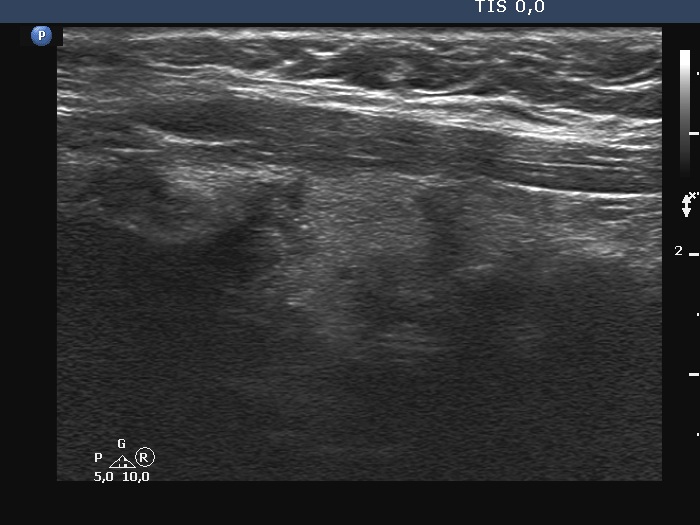

100 consecutive cases of papillary cancer - case 100 (ultrasonographic picture 6)

Left lobe, longitudinal scan. There at least three, relatively large discrete hypoechoic lesions. The middle one is suspicious due to the presence of microcalcifications and irregular borders.